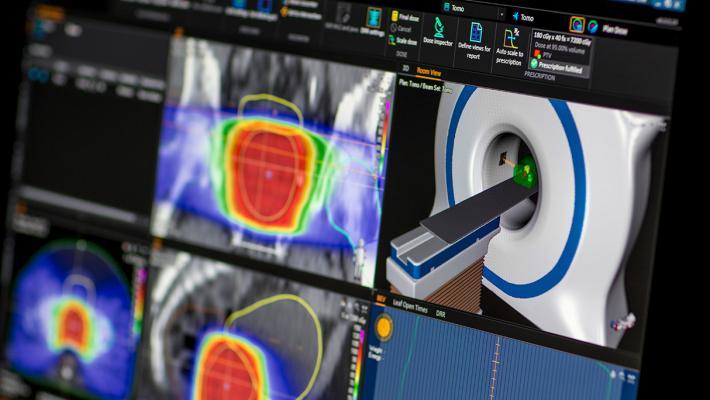

Treatment planning systems are at the heart of radiation therapy (RT) systems and the key to improved patient outcomes ...